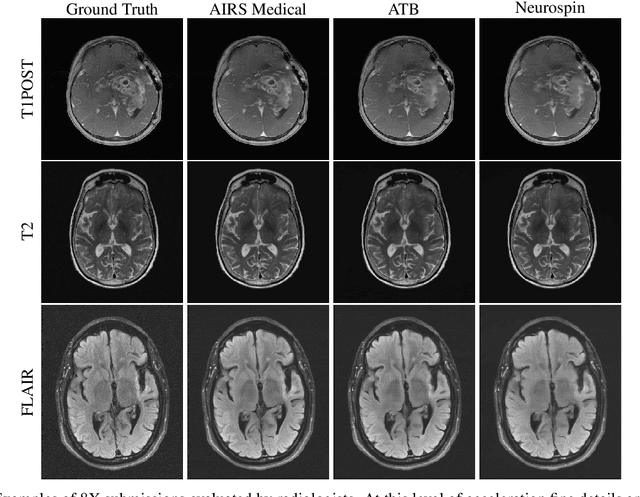

Abstract:Accelerating MRI scans is one of the principal outstanding problems in the MRI research community. Towards this goal, we hosted the second fastMRI competition targeted towards reconstructing MR images with subsampled k-space data. We provided participants with data from 7,299 clinical brain scans (de-identified via a HIPAA-compliant procedure by NYU Langone Health), holding back the fully-sampled data from 894 of these scans for challenge evaluation purposes. In contrast to the 2019 challenge, we focused our radiologist evaluations on pathological assessment in brain images. We also debuted a new Transfer track that required participants to submit models evaluated on MRI scanners from outside the training set. We received 19 submissions from eight different groups. Results showed one team scoring best in both SSIM scores and qualitative radiologist evaluations. We also performed analysis on alternative metrics to mitigate the effects of background noise and collected feedback from the participants to inform future challenges. Lastly, we identify common failure modes across the submissions, highlighting areas of need for future research in the MRI reconstruction community.